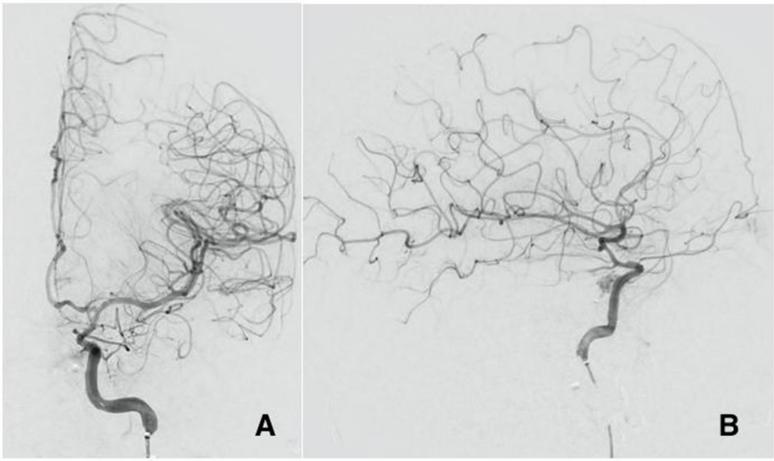

经过多学科讨论后,决定尝试使用分流支架修复tCCF,该支架可优化受损左脑的血流,并在需要时提供适当的BTO。展开支架后,立即注意到流向左脑的流量有所改善(图3A、B)。患者开始接受双重抗血小板治疗以保持支架通畅。

图3. 脑血管造影AP视图(A)和侧视图(B)。在假性动脉瘤破裂部位进行分流支架植入术后,瘘管内的流量显著减少,脑灌注改善